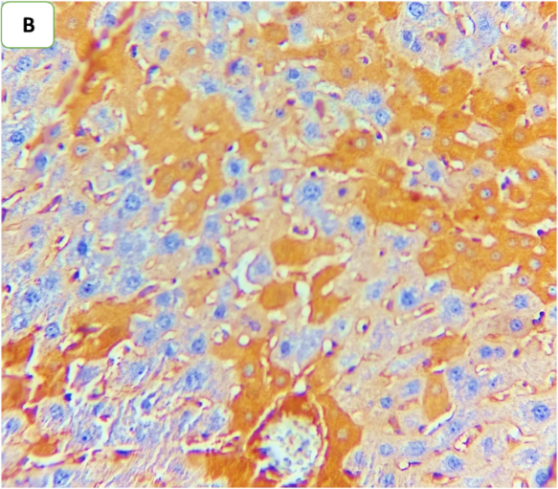

Ertugliflozin mitigated sepsis-induced activation of ERK1/2 in hepatic tissue

Immunohistochemical analysis revealed a significant increase in phospho-ERK 1/2 in the hepatic tissue of the CLP and CLP+DMSO groups compared with that of the sham group. Conversely, ertugliflozin therapy significantly diminished the sepsis-induced increase in nuclear expression and activation of ERK1/2 (fig. 7 and fig. 8).

Fig. 8: Effect of ertugliflozin on phospho-ERK1/2 by immunohistochemistry (five animals in each group): A. CLP group: animals underwent CLP-induced sepsis; the mean quick H score of nuclear expression for this group was 54, with moderate-intensity nuclear expression in 20% of the examined tissue (black arrows). B. Sham group: animals in this group were anaesthetized only and then laparotomized without the induction of sepsis by CLP, and the mean quick H score of nuclear expression was zero. C. CLP+ertugliflozin group: animals were intraperitoneally injected with ertugliflozin (20 mg/kg) for 1 hr before CLP, the mean quick H score of nuclear expression for this group was 7, with liver tissue with 5% intense nuclear expression (black arrow). D. CLP+DMSO group: animals were intraperitoneally injected with DMSO (vehicle for ertugliflozin) for 1 hr before CLP, the mean quick H score of nuclear expression was 40.8, indicating that strong nuclear staining (black arrows) was present in the liver tissue. A, B, C, D X 400, IHC